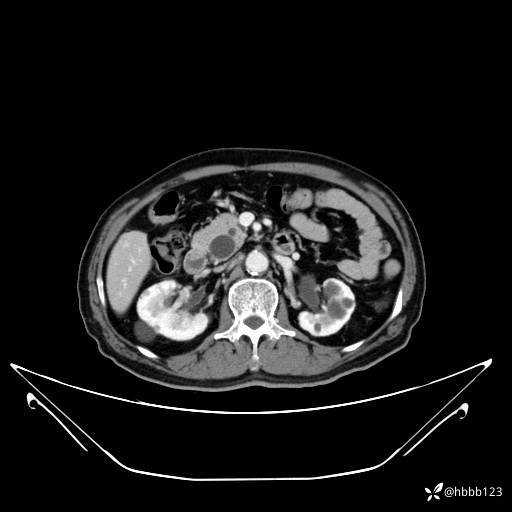

门脉期: